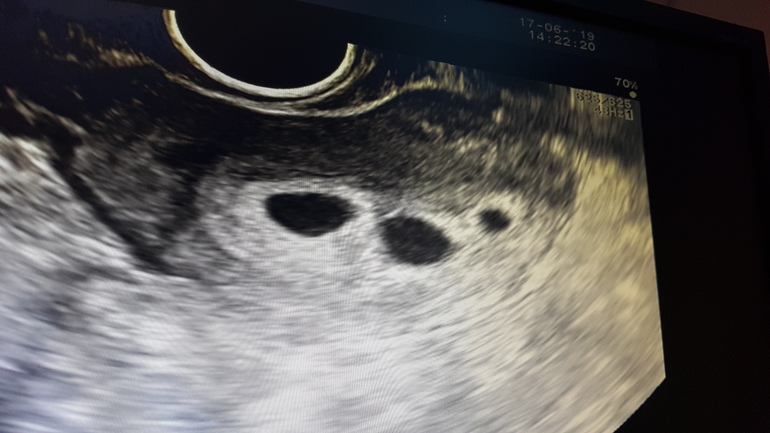

Девочки, вопрос такой. 24 мая перенесли 2 бластоцист аб, сегодня 6 недель беременности, по узи 3!!! плодных яйца.

2 соответствуют сроку, эмбрион, желт.мешочек и сердцебиение определяется.

3е плодное яйцо отстающее 5 мм (на 4 недели).

П.с. повторили узи через неделю, ситуация та же, 2 пя с э и сб соотвествуют сроку, 2 увеличилрсь до 10 мм, но э и сб нет, пя со взвесью по структуре.